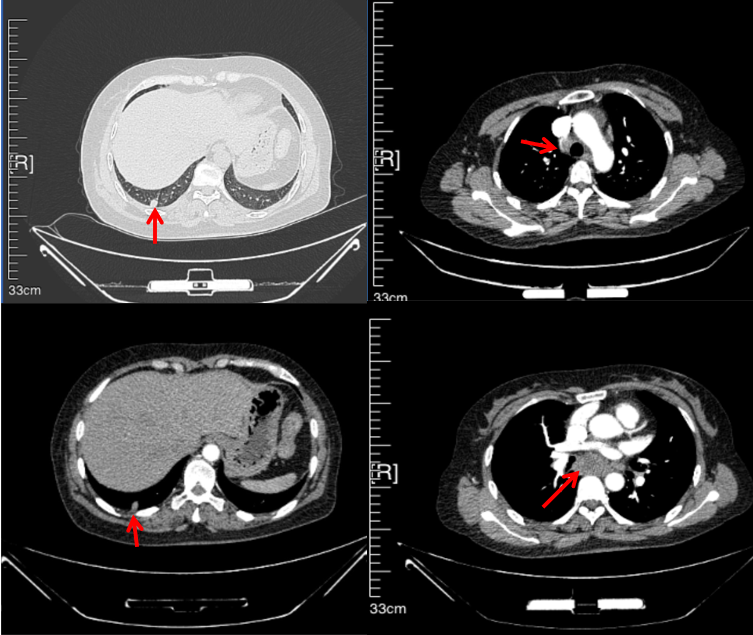

56岁,女性,无吸烟史饮酒史,既往体健。2023年02月患者体检发现肺占位性病变,胸部增强CT:右肺下叶后基底段结节;右侧锁骨上及纵隔内多发淋巴结肿大。PET-CT:右肺下叶周围型肺癌可能性大;1R、2L、3P、4R、4L及7组淋巴结转移可能性大。2023年02月就诊于本院胸外科行超声胃镜下纵隔肿物穿刺活检术,病理:结合免疫组化,符合肺腺癌。行NGS基因检测:EML4:exon20-ALK:exon20融合。PD-L1(克隆号22C3)TPS=55%。

2023年2月20日基线检查

2024年6月复查PR(最佳疗效)

2024年12月复查维持PR

2025年3月复查维持PR